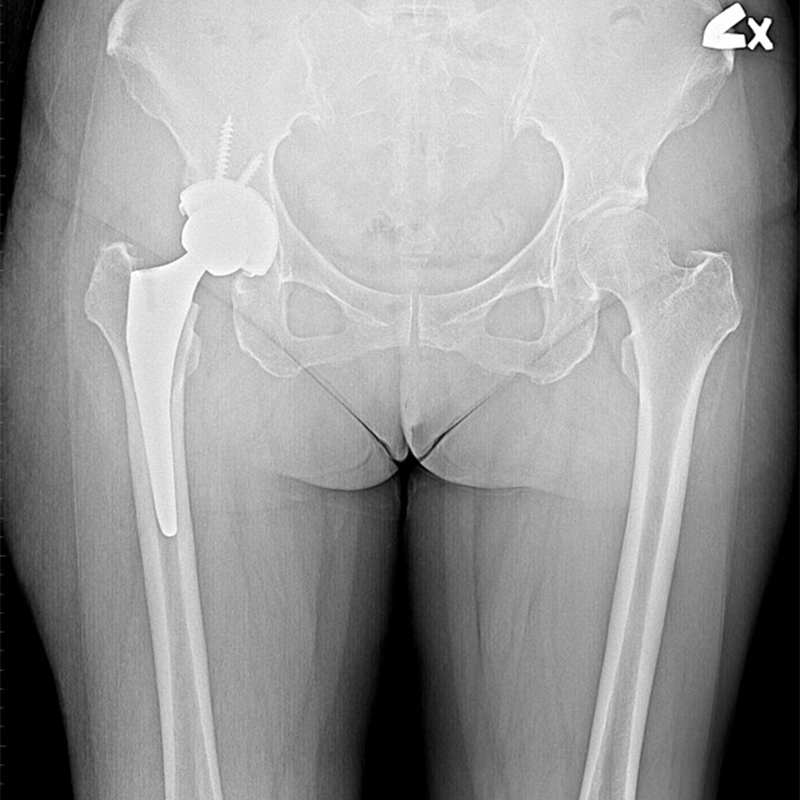

機器手臂手術 首頁 案例分享 髖關節手術 機器手臂手術 72歲 楊女士 退化性關節炎 術前 術後 60歲 彭先生骨股頭壞死 術前 術後 53歲 王女士退化性關節炎(DDH先天發育不全 CROWE TYPE 2) 術前 術後 83歲林女士退化性關節炎 術前 術後 83歲林女士退化性關節炎 術前 術後 楊女士 70歲 術前 術後 蔡女士 60歲 術前 術後